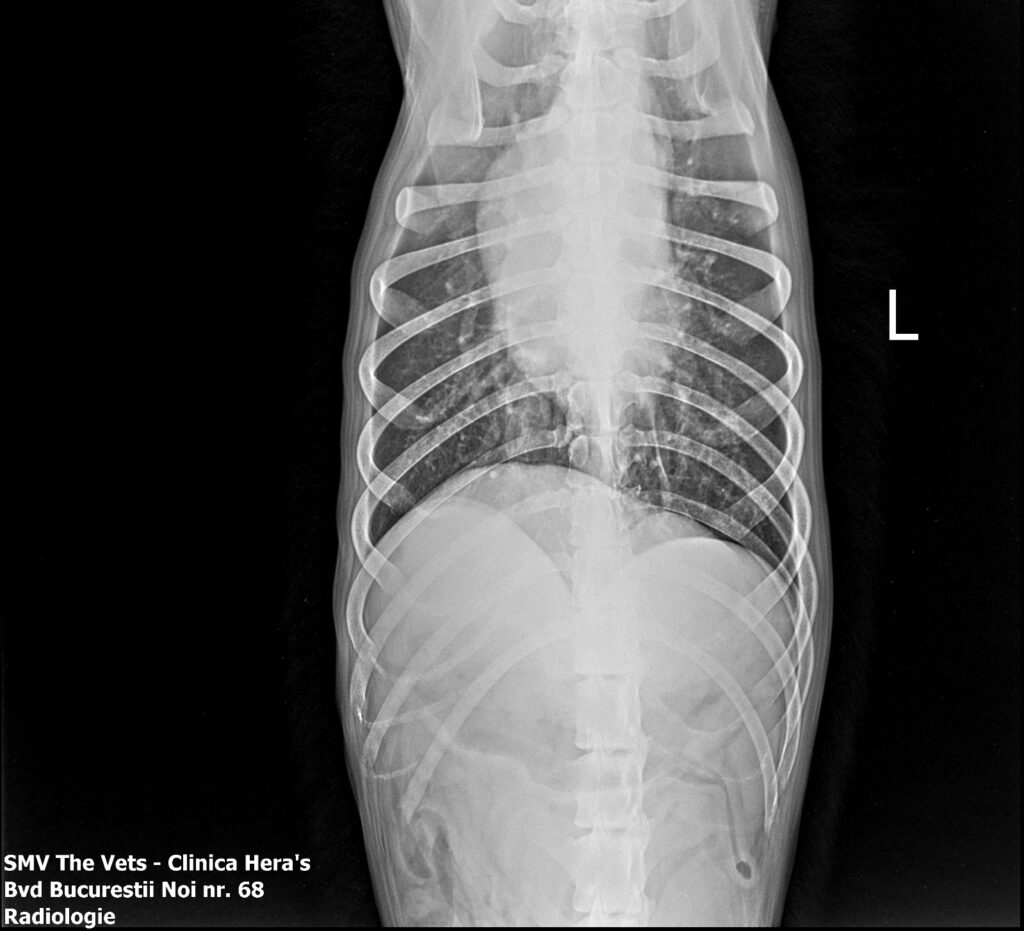

Radiografia (RX) este o investigație imagistică ce folosește raze X pentru a vizualiza structurile interne ale corpului: oase, organe, torace și cavitatea abdominală.

Imaginea obținută îi permite medicului să observe modificări ce nu pot fi depistate prin simpla examinare fizică.

Aparatul RX trimite raze X prin corpul animăluțului, iar țesuturile absorb diferit aceste raze.

Oasele apar albe (absorb mult)

Aerul apare negru

Organele moi apar în nuanțe de gri

Imaginea finală ajunge pe un ecran digital, unde medicul o poate analiza în detaliu.

3.3. Afecțiuni toracice

Pentru afecțiunile toracice, radiografia permite evaluarea plămânilor și a inimii, fiind utilă în diagnosticarea bolilor pulmonare, a problemelor cardiace sau a prezenței lichidului în cavitatea toracică.